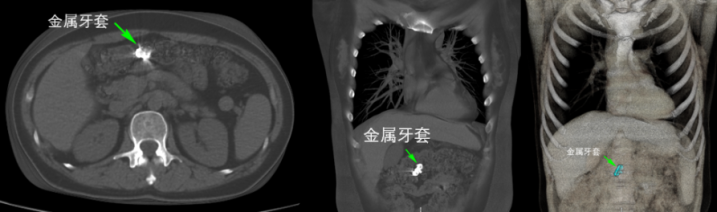

病例三:40岁的田女士吃柿子时失慎将更正牙套吞下,出现腹部不适,CT在横结肠内发现款属异物。